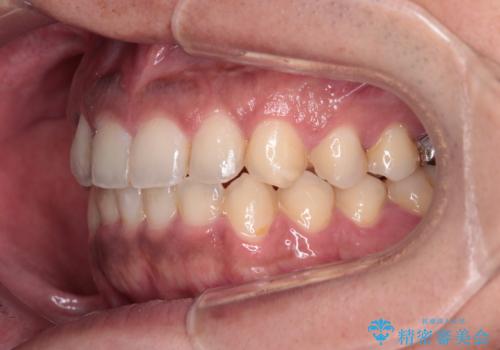

- 前歯のデコボコを気にして来院された患者様です。

前歯が90度近く捻れていたため、しっかりと治すことを考えるとワイヤー矯正の方がおすすめではありましたが、本人の希望によりインビザラインを用いて矯正治療を行うこととしました。

インビザラインは、十分な装着時間が達成されると前歯のデコボコをしっかりと改善できますが、1日の装着時間が20時間に達しなくなると、不十分な仕上がりとなるため、しっかりと装着するよう指示をしました。

途中2年強の来院がなく、改善されていたデコボコが元に戻ったり、装着時間が不足しており前歯のデコボコは十分に改善することはできませんでしたが、5年間の有効期限内で可能な限り歯列を整えることができました。